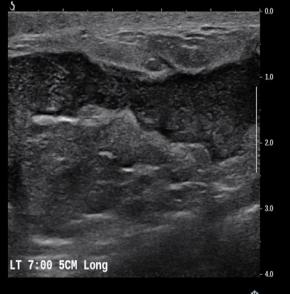

[Breast] 35 /F, Palpable mass, left with redness

Diagnosis Idiopathic granulomatous mastitis

Comments Idiopathic granulomatous mastitis (IGM) is a rare benign inflammatory breast entity characterized by lobulocentric granulomas. IGM has a persistent or recurrent disease course and affects parous premenopausal women with a history of lactation. It has also been associated with hyperprolactinemia. The most common clinical sign is a palpable tender mass. However, the nonspecific manifestations and varied demographic features of this condition, as well as the other similar-appearing and superimposed breast entities, pose substantial diagnostic challenges. Entities with similar manifestations include inflammatory breast cancer (IBC), infective mastitis, foreign body injection granulomas, mammary duct ectasia, diabetic fibrous mastopathy, and systemic granulomatous processes. The strategy for imaging IGM depends on patient age, clinical manifestations, and risk factors. Targeted ultrasonography, mammography, and less commonly, magnetic resonance imaging have proven to be useful for imaging evaluation. Core-needle biopsy, with or without fine-needle aspiration for cytopathologic examination, and culture analysis are usually required to exclude IBC and other benign inflammatory breast processes. Patients with IGM have an excellent prognosis when they are appropriately treated with oral steroids or second-line immunosuppressive and prolactin-lowering medications. However, surgical excision may be an option for patients in whom medication therapy is unsuccessful. Imaging surveillance can be offered to patients with incidentally encountered IGM or mild symptoms. Clinical suspicion for this rare disease and the breast imager’s prompt diagnosis can lead to an improved patient outcome. The purpose of this article is to review the imaging manifestations of IGM in a multimodality case-based format and to describe relevant clinical and imaging-based differential diagnoses. The associated pitfalls, epidemiologic and histopathologic factors, clinical manifestations, natural course, and management of IGM also are discussed.